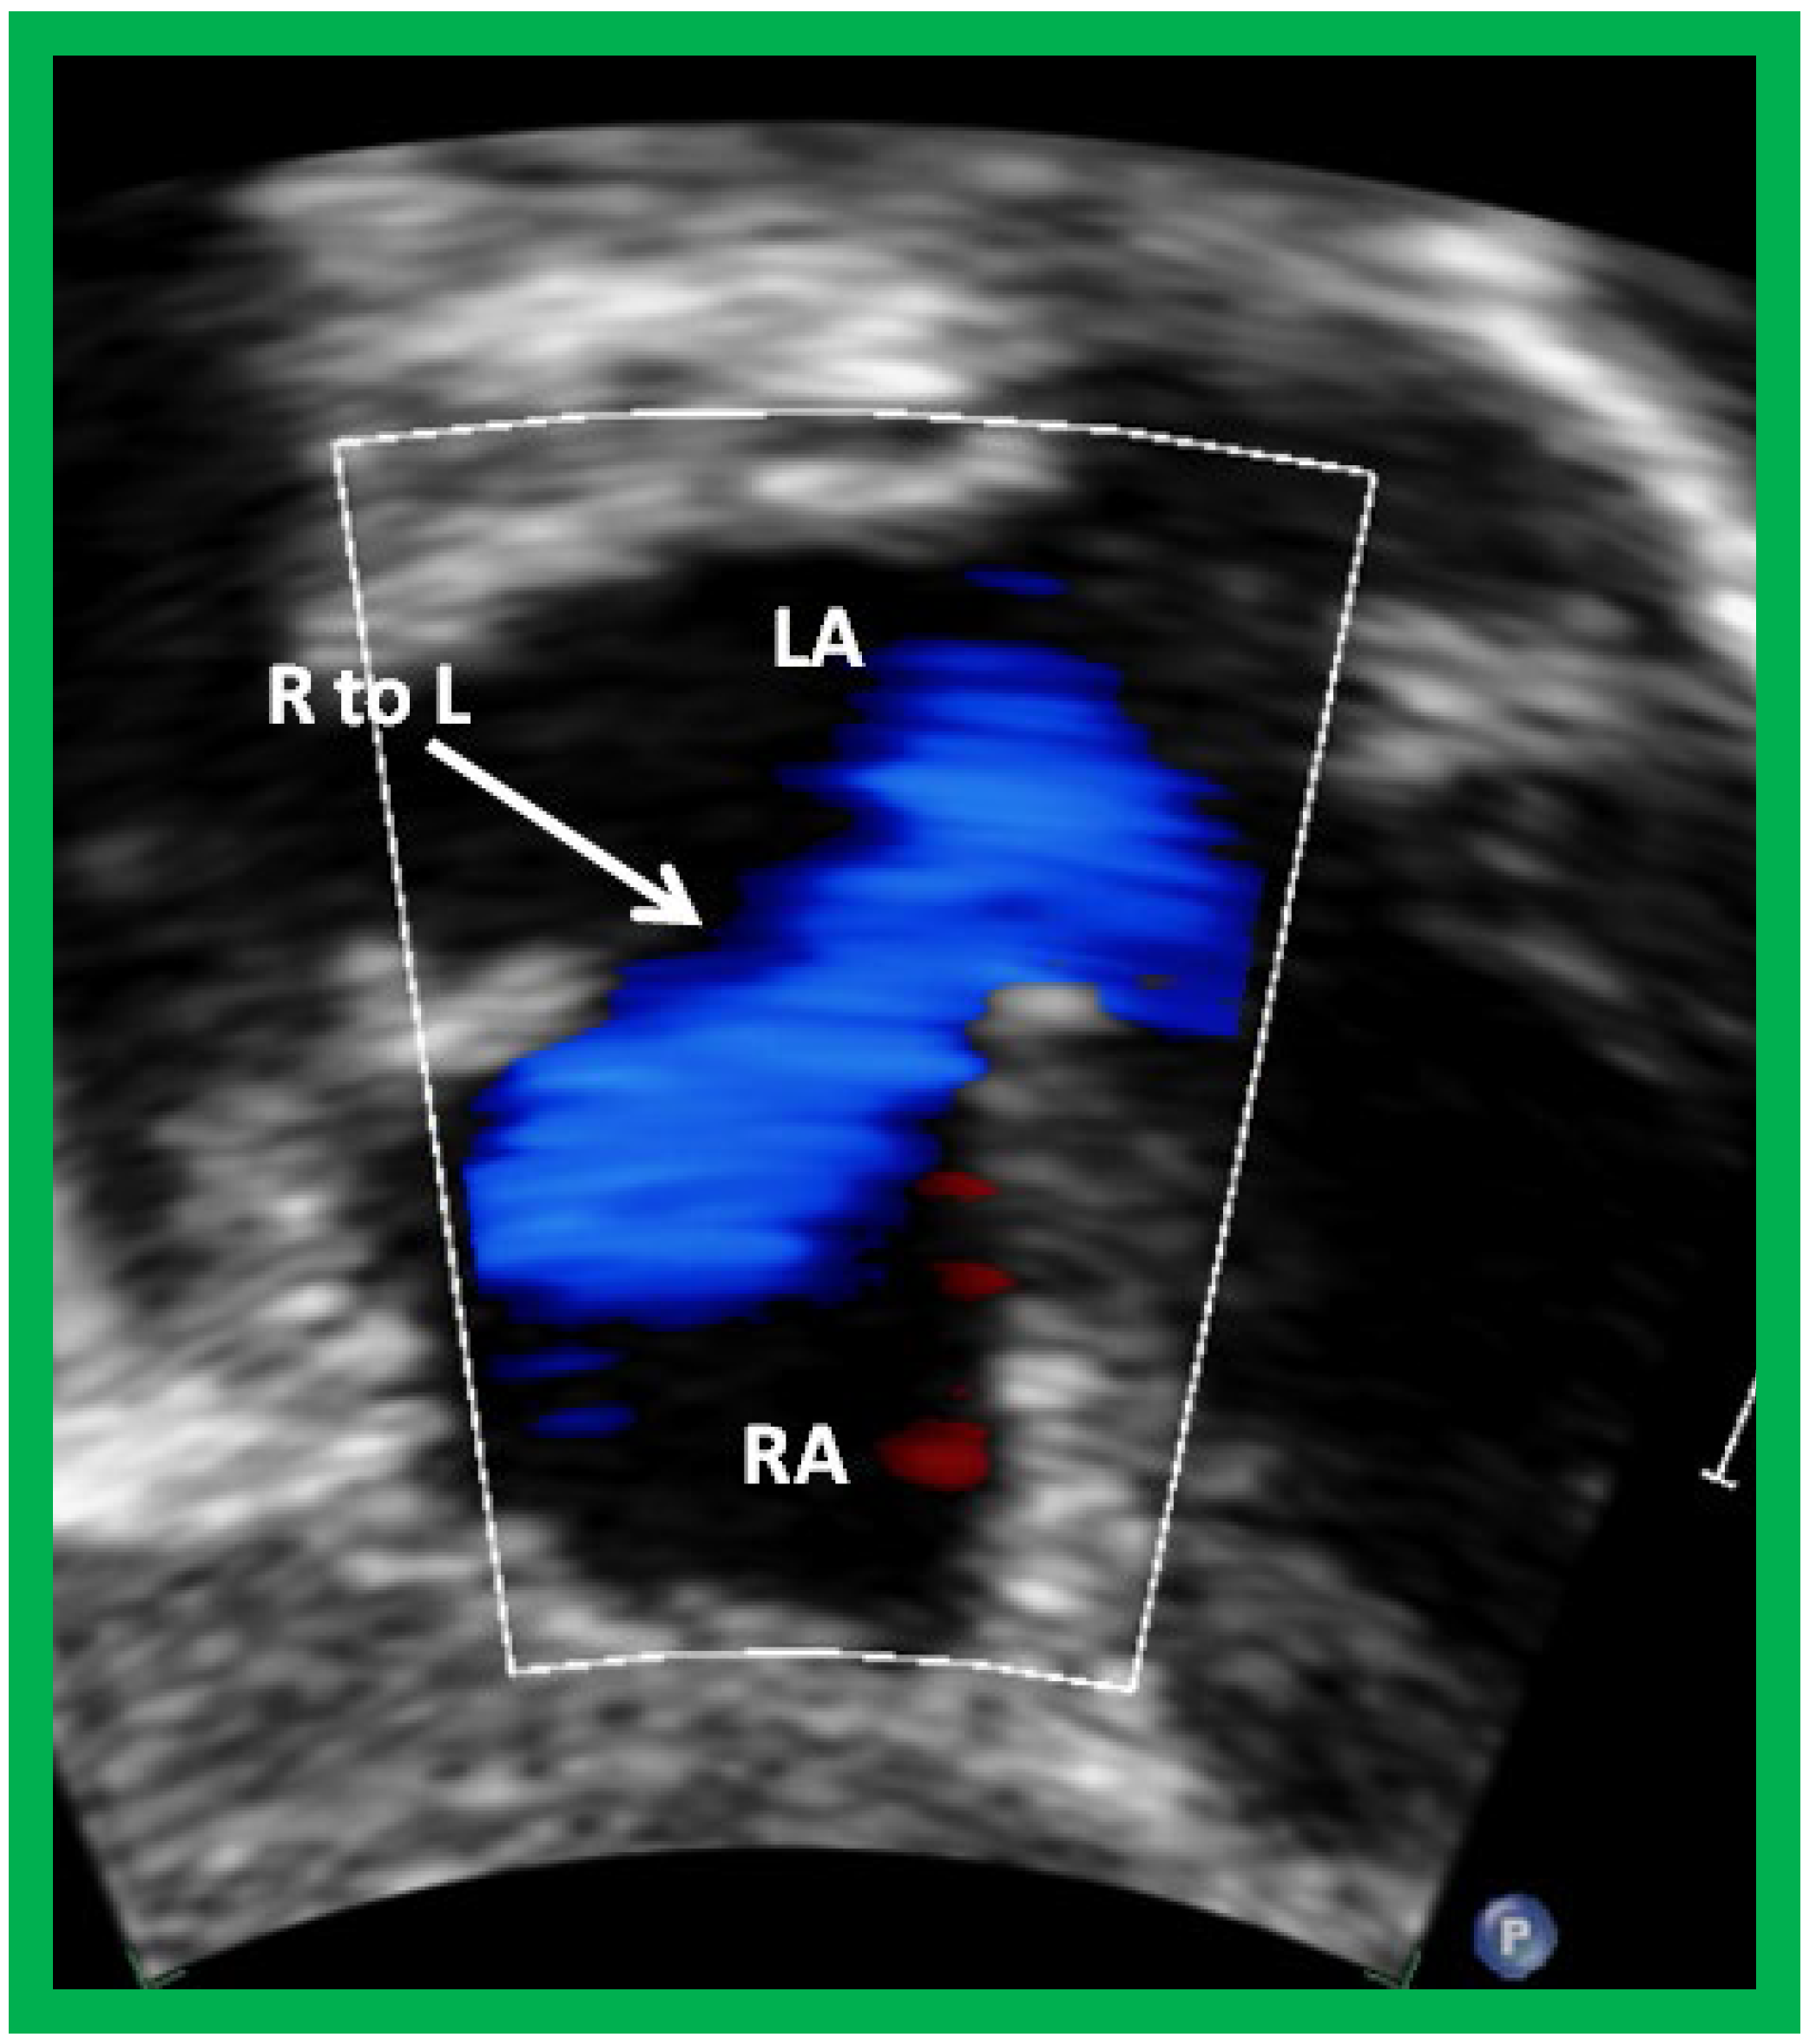

Following the demonstration of the atretic tricuspid valve, the sizes of the cardiac chambers are evaluated both by M-mode (Z scores) and 2D echocardiography; an enlarged RA, LA and LV and a small RV are seen. Pulsed (not shown) and color Doppler ( Figure 5 ) studies are helpful in illustrating right to left shunt across a PFO or an ASD.

Figure 4. Selected video frame from subcostal view of a patient with tricuspid atresia demonstrating right to left (R to L) shunt (arrow) across the interatrial communication. LA, left atrium; RA, right atrium. Reproduced from Reference [21].